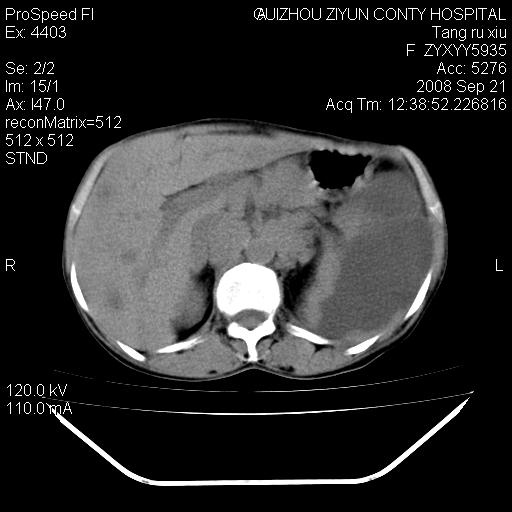

f、57岁,上腹痛.2月,近来胸闷。2月前在外院摄胸片示左侧胸腔少量积液。

(患者腹痛入院,欲吐,临床医生说禁饮,所以没有口服对比剂)

肝脏大小形态尚可,其实质内可见多发大小不等的低密度影,边缘模糊。肝门区结构紊乱,腔静脉腹主动脉旁可见多发软组织密度影,部分融合成团块状,并向下延伸。胰腺及十二指肠结构显示不清。腹腔内脐后肠管走形僵硬,管壁可见增厚。盆腔内可见多个淋巴结影。所扫层面左侧胸腔可见大量弧形水样密度影,其内侧可见被压缩的肺组织影。左侧胸壁可见一小结节样软组织密度影,边缘模糊。心脏纵隔向右侧移位。心脏包膜内可见囊样低密度影,其内侧心房室周围可见一圈气体样密度影。纵隔内大血管旁可见多发软组织团块影,部分融合。

1.腹膜后淋巴瘤侵及肝脏,肺内及纵隔内多发转移。2.左侧大量胸腔积液并压缩性肺不张。3.心包脓肿可能,转移不除外。4.脐后局部肠管管壁增厚,考虑炎症可能,肿瘤不除外。